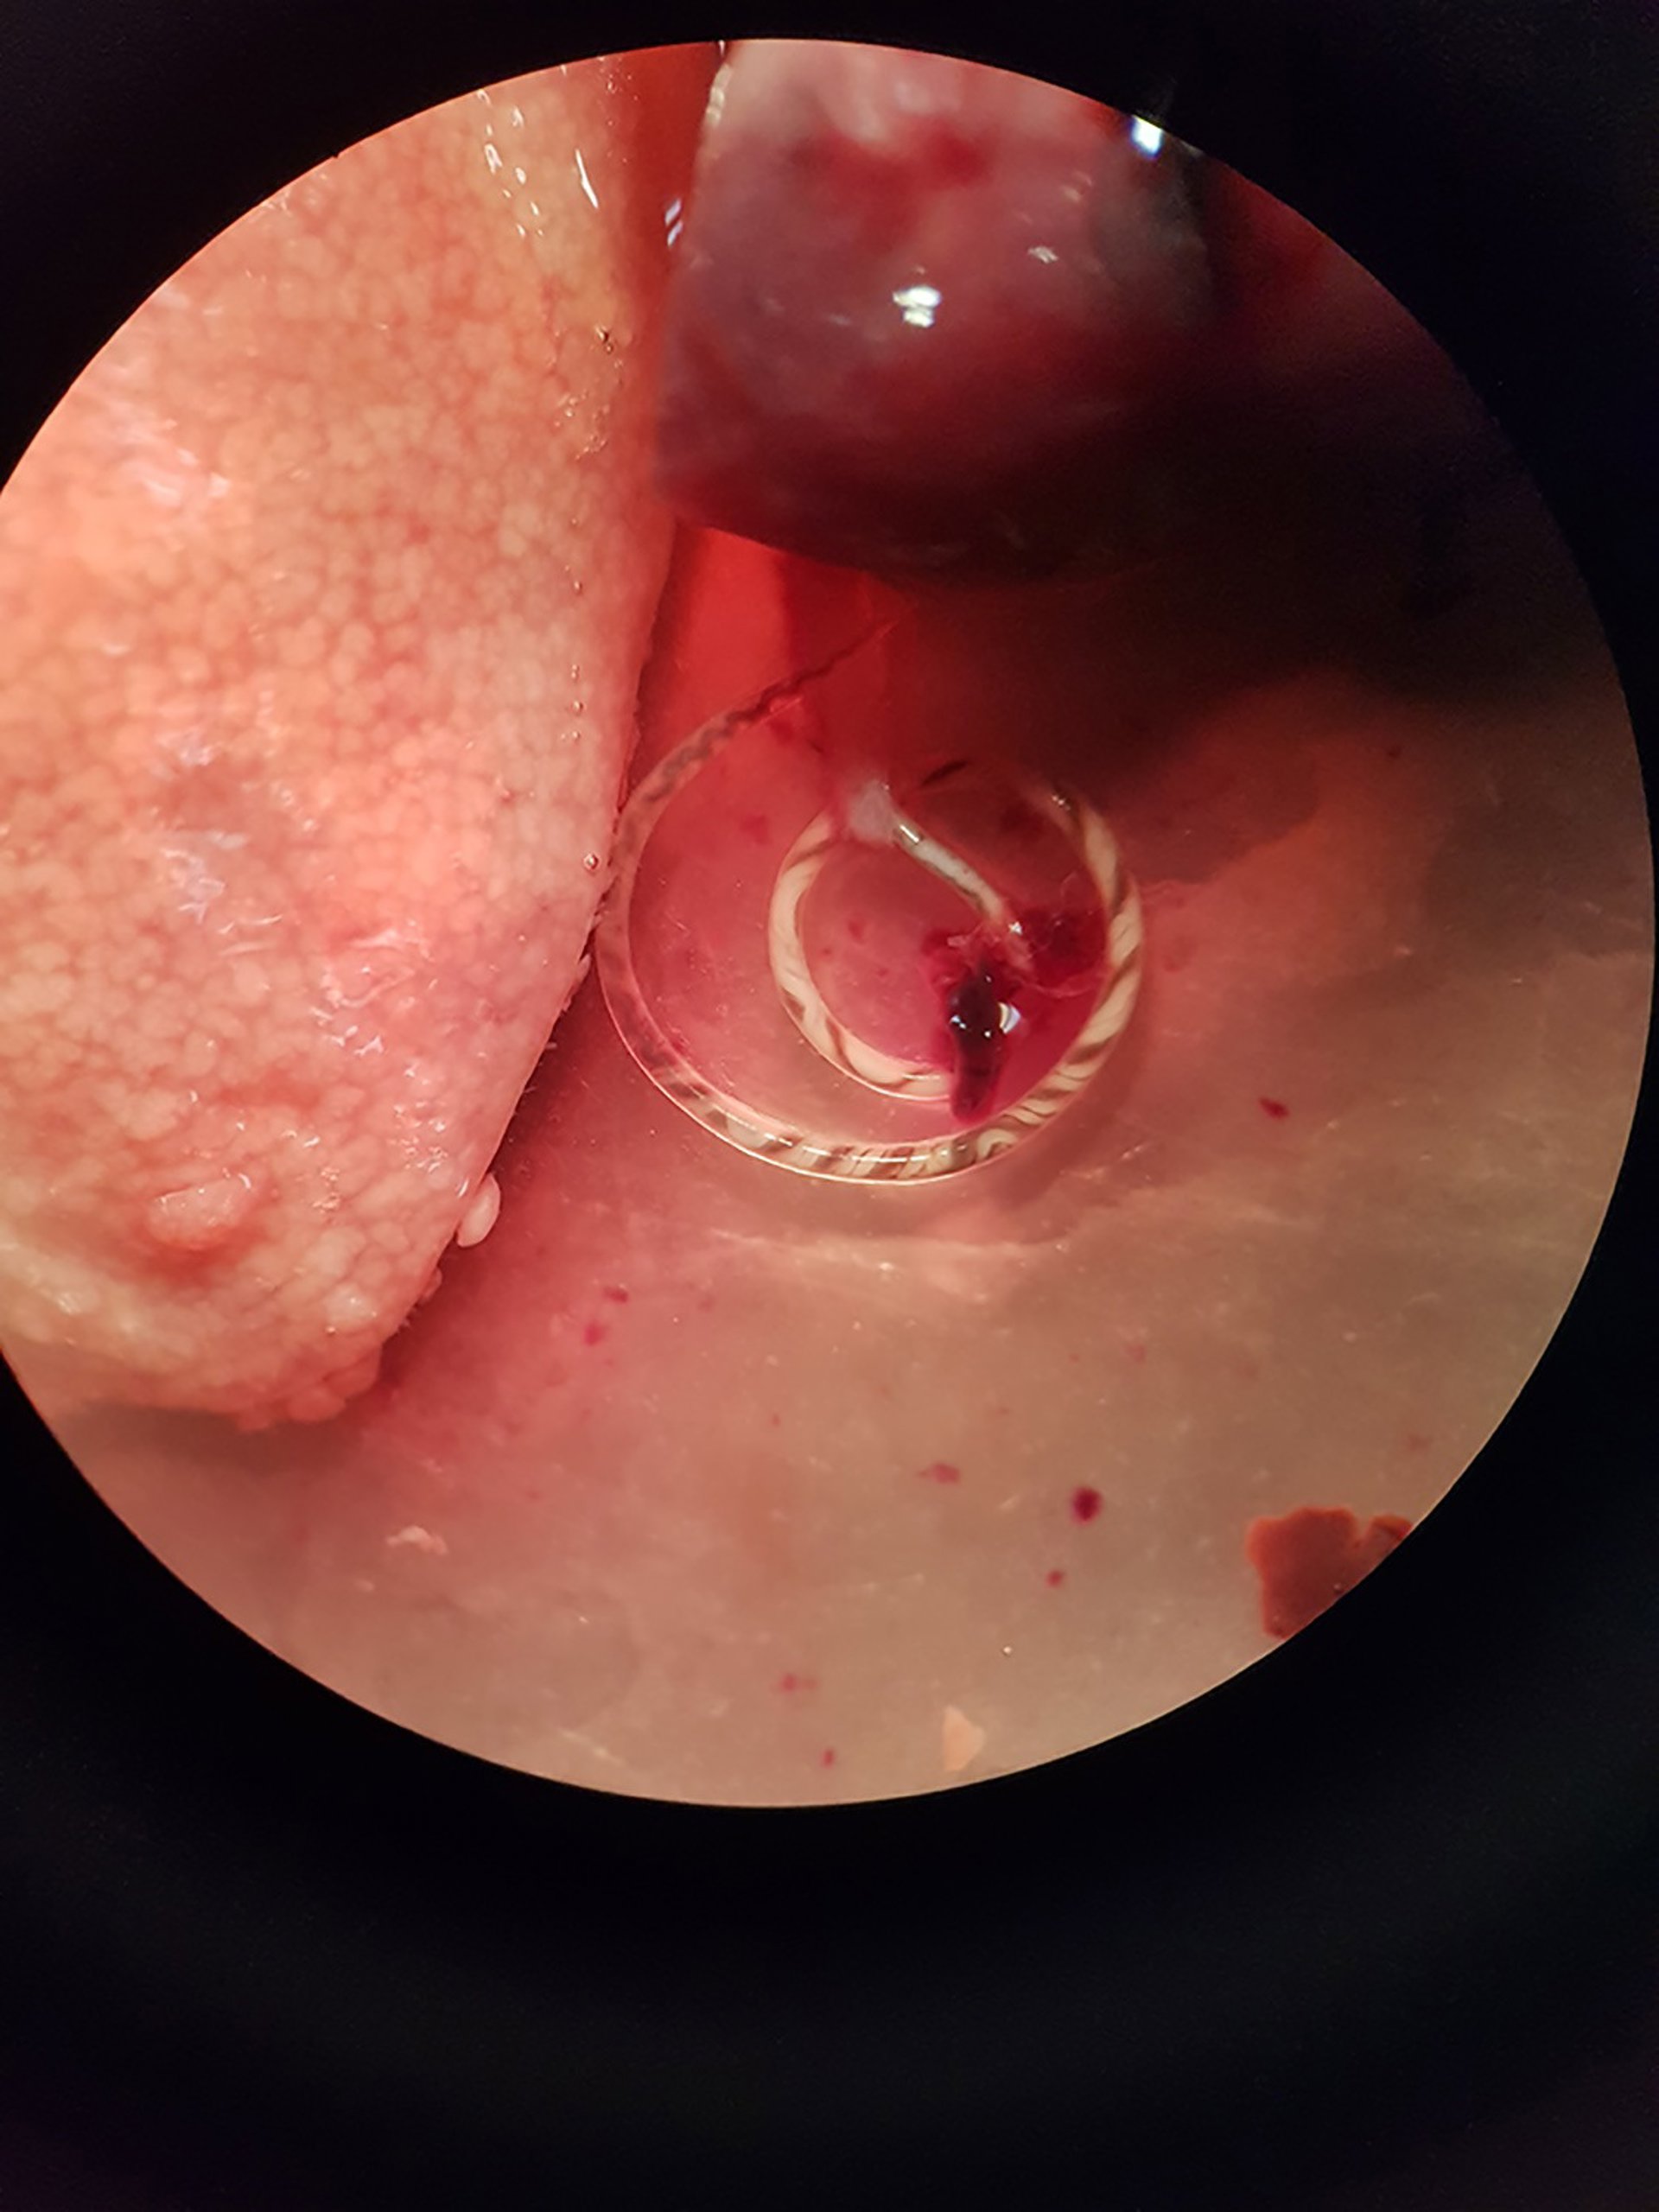

Una investigación liderada por el grupo Parásitos y Salud de la Universitat de Valncia (UV) ha hallado por primera vez en Europa continental el nematodo (gusano) Angiostrongylus cantonensis, un parásito zoonótico capaz de ser transmitido al ser humano que está presente en las arterias pulmonares de las ratas y que es el agente causal más común en el ser humano de la meningitis eosinofílica (ME).

En concreto, el parásito se ha localizado en dos especies de ratas de la ciudad de Valncia. Esta enfermedad provoca una inflamación de la membrana que cubre el cerebro y puede causar ataques, lesiones cerebrales y trastornos visuales, entre otros síntomas.

El grupo de investigación Parásitos y Salud, del departamento de Farmacia de la UV, trabaja en colaboración con el servicio de Sanidad del Ayuntamiento de Valncia y la empresa Laboratorios Lokímica --responsable del control de plagas-- en un estudio parasitológico de los roedores en la ciudad. El descubrimiento del nematodo, de importante repercusión en salud pública, se ha dado tanto en ratas de alcantarilla (Rattus norvegicus) como en la rata negra (Rattus rattus).